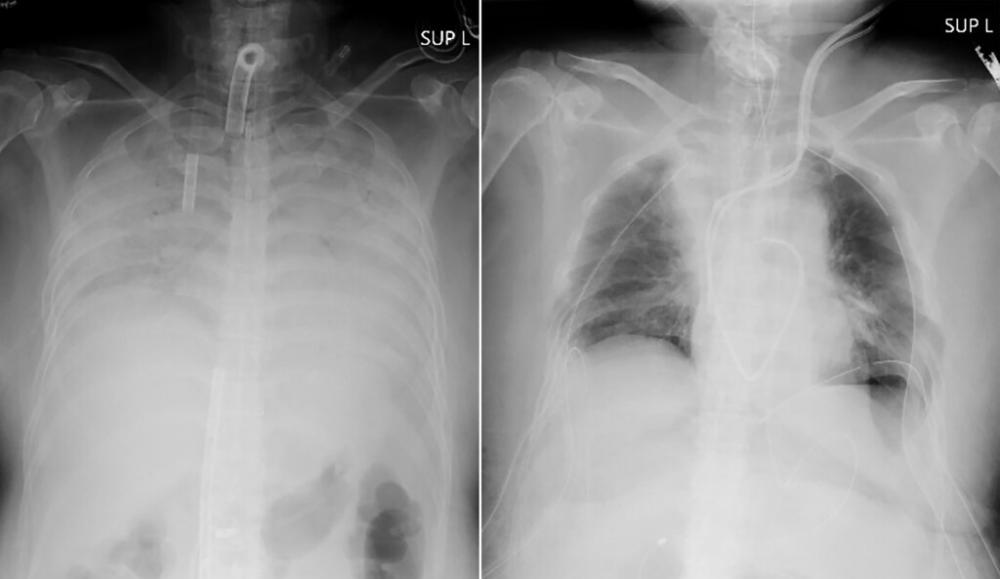

The recipient, identified only as a woman from Japan's western region of Kansai, is recovering after the nearly 11-hour operation on Wednesday, Kyoto University Hospital said in a statement. It said her husband and son, who donated parts of their lungs, are also in stable condition.

Her husband and son volunteered to donate parts of their lungs, and the surgery was conducted at Kyoto University Hospital by a 30-member team headed by Dr. Date. Her husband donated part of his left lung, and son gave part of his right lung.

She is expected to be able to leave the hospital in about two months and return to her normal life in about three months, the university said.